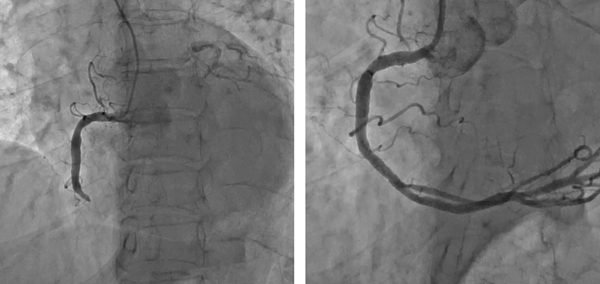

본격적인 추위가 시작되면서 일교차도 크게 벌어졌다. 이때 주의해야 할 것이 바로 심뇌혈관질환이다. 통계청에 따르면 2017년 심뇌혈관질환으로 사망한 사람 수는 7월(4377명)과 8월(4348명)에 가장 적었고, 12월(5775명)과 1월(5660명)에 가장 많았다. 사망자가 겨울에 많은 이유는 기온이 내려가면서 혈관이 급격히 수축되기 때문이다. 좁아진 혈관으로 혈액이 흐르다가 심장 혈관이 막히면 급성심근경색이 발생하고, 또 좁아진 혈관으로 많은 혈액을 보내기 위해 심장이 무리하게 되면서 여러 심장병 발생 위험이 높아진다. 심뇌혈관질환 중에서도 돌연사 원인의 80~90%를 차지하는 '급성심근경색'에 대해 알아본다. ◇ 급성심근경색, 즉시 치료해도 사망률 30~40% 간혹 건강했던 사람이 갑자기 사망했다는 이야기를 들을 때가 있다. 이런 돌연사의 경우 대부분 겉으로는 건강해 보였을지 몰라도 몸 안에서는 여러 문제가 발생하고 있는 경우가 많다. 인천성모병원 심장혈과내과 이관용 교수는 "특히 돌연사의 80~90%를 차지하는 급성심근경색은 발견 즉시 치료를 해도 사망률이 30~40%가 넘고, 증상이 심각하면 1~2시간 이내에 사망할 수도 있다"며 "급성심근경색은 누구도 예외일 수 없기 때문에 평소에 심근경색에 대해 바로 알고 예방하는 습관을 가져야 한다"고 말했다. 심장은 크게 세 가닥의 관상동맥을 통해 필요한 산소와 영양분을 공급받는데, 관상동맥이라는 이름은 세 가닥의 동맥이 심장을 관처럼 감싸고 있다고 해서 붙여졌다. 관상동맥 혈관 벽에 콜레스테롤이 침착되면 '죽상반'이 생성된다. 죽상반은 산화된 콜레스테롤이 혈관으로 침투해 뭉쳐서 죽같이 끈적끈적한 덩어리가 되고, 딱딱한 섬유질이 덮개처럼 덮인 것을 말한다. 혈관이 좁아지다가 염증으로 인해 죽상반이 터지고 혈전(피떡)이 생성되면 혈관이 완전히 막힐 수 있다. 이렇게 막힌 혈관 때문에 심장 근육(심근)에 혈액공급이 제대로 되지 않으면 심장 조직이 괴사한다. 즉, 심근경색은 관상동맥의 내부가 혈전으로 완전히, 또는 부분적으로 막혀 심장 조직이나 근육이 썩는 질환이다. 죽은 심장근육은 다시 살아나지 않는다. ◇ 사람마다 심근경색 증상 달라 급성심근경색은 특별한 증상 없이 갑자기 발병하는 경우가 많다. 이관용 교수는 "혈관에 노폐물이 쌓여 있지만 혈액순환장애를 일으킬 정도로 심하지 않은 경우에는 증상을 느끼기 힘들다"고 말했다. 또한 증상은 사람이나 질환의 상태에 따라 다르게 나타날 수 있다. 대표적인 증상은 가슴을 쥐어짜는 듯한 통증이다. 심한 가슴 통증은 30분 이상 지속되기도 하며, 대부분 호흡곤란과 함께 나타난다. 또 가슴의 정중앙이나 약간 좌측에서 시작된 통증은 어깨나 목, 팔로 퍼져나가는 방사통을 일으키기도 하고, 호흡곤란이나 심장 두근거림, 식은땀, 구역질, 어지러움, 소화 불량 등이 함께 생기기도 한다. 환자에 따라서 가슴 통증을 호소하기 전에 갑작스러운 의식 불명이나 심장마비로 응급실에 실려 가는 경우도 있다. 이관용 교수는 "많은 사람이 가슴 통증을 소화불량으로 오인해 치료 시기를 놓친다"며 "가슴 통증 없이 구토를 하거나, 소화가 안 되는 느낌, 속이 쓰린 느낌, 명치나 턱 끝이 아픈 경우도 있어 심근경색 위험군일 경우 미리 심장 검사를 받는 것이 좋다"고 말했다. ◇ 고혈압, 당뇨병 등 있으면 심근경색 위험 6배 급성심근경색의 위험을 높이는 요소에는 흡연, 고지혈증, 고혈압, 당뇨병 등이 있다. 만성질환이 있으면 일반인보다 심근경색 확률이 6배 정도로 높다고 알려졌다. 또 가족 중 심장질환으로 사망한 사람이 있다면 위험이 3~4배 높고, 비만, 육식 위주의 식습관 등도 심근경색의 위험을 높인다. 이관용 교수는 "이렇게 위험 요소가 많은 환자는 애매한 흉통이 있다면 선별검사를 통해 심근경색 위험을 예측할 수 있다"며 "운동부하검사와 관상동맥 CT 검사가 있다"고 말했다. 최근 선별적인 고위험 환자에서는 증상이 없어도 관상동맥 CT 검사를 통해 추후 심근경색 및 심혈관 합병증의 위험을 예측할 수 있는 연구들이 발표됐다. ◇ 스텐트 삽입해 혈관 뚫는 치료 행해져 극심한 가슴 통증이 지속되면 최대한 빨리 관상동맥중재술이 가능한 병원으로 가야 한다. 급성심근경색으로 진단되면 막힌 혈관에 스텐트(금속 그물망)를 넣어 혈전으로 막힌 혈관을 뚫고 다시 피가 흐를 수 있도록 한다. 이렇게 스텐트로 막힌 관상동맥혈관을 뚫는 것이 관상동맥중재술이다. 급성심근경색으로 심장마비가 발생하면 4분 이내 심폐소생술과 함께 가능한 한 빨리 막힌 심장혈관을 뚫어야 한다. 심장동맥 폐쇄가 시작된 지 20분 이내에 심장 근육의 안쪽에서부터 괴사가 시작돼 2~4시간 후에는 바깥쪽까지 진행해 심장 근육 전체가 손상된다. 대개 발병 직후 병원에 도착하기 전에 약 30%가 사망하며, 병원에 도착해서 적극적인 치료를 하더라도 사망률이 5~10% 이른다. 이관용 교수는 “과거에는 심근경색증을 치료하기 위해 혈전 용해제를 많이 사용했지만 일부 환자에선 효과가 적고, 고위험 환자에서는 뇌출혈의 위험성이 있으며, 혈전이 뚫리더라도 시간이 오래 걸려 치료 효과가 떨어졌다"며 "최근엔 말초 혈관을 통한 시술인 관상동맥중재술을 주로 시행한다”고 말했다. |